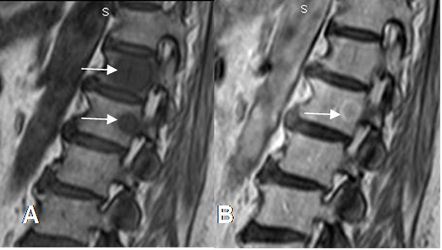

Fig 229. Tumor metastásico.

A: RM sagital en T1. Lesiones hipointensas en D12 y L1, por enfermedad metastásica de próstata.

B: RM sagital en T1 con contraste. Realce con halo hiperintenso, signo de enfermedad metastásica.